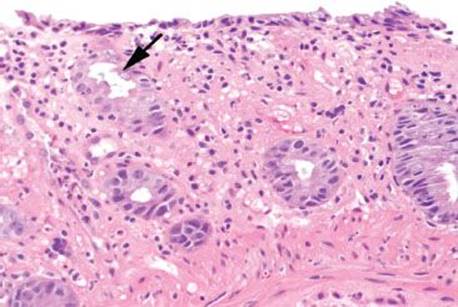

Figure 4.51 Ischemic colitis pattern. The striking finding at low magnification is the presence of “microcrypts” (arrow). Note the collapse of the hyalinized lamina propria in this area, causing a condensation of these crypts. Look at the left portion of this image for contrast to relatively normal crypts and lamina propria.

Mucosal ischemia causes a highly characteristic pattern of injury, including features of surface injury, loss of mucin, lamina propria hemorrhage and hyalinization, withered crypts, atrophic microcrypts, and lamina propria collapse (Fig. 4.50). The architectural pattern of withered crypts and microcrypts is distinctive at low magnification, and one might even refer to this pattern of injury as the “microcrypt pattern” (Fig. 4.51). Although ischemic injury is top among the differential diagnoses, other considerations include vascular injury (such as that seen in radiation colitis, amyloidosis, or vasculitis), infection (particularly Escherichia coli 0157:H7 and Clostridium difficile), and medications (NSAIDs, Kayexalate, and sevelamer).